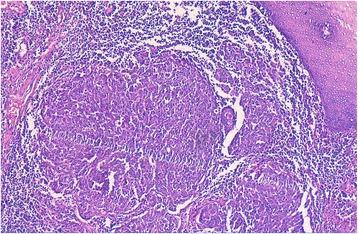

An 81-year-old Morrocan man, smoker for 40 years, presented with a 1 year history of dysphonia, dyspnea and dysphagia. Laryngoscopy showed a mass occupying supraglottic, glottic and subglottic levels of the larynx. Cervico-thoracic computed tomography scan showed a laryngeal wall thickening with cervical lymphadenopathy. Laryngeal biopsy was performed. Microscopic analysis and immunohistochemistry confirmed the diagnosis of laryngeal lymphoepithelial carcinoma. Immunostaining for LMP1 was negative.

一名81岁的摩洛哥男性,有40年吸烟史,出现声音嘶哑、呼吸困难和吞咽困难1年。喉镜检查显示喉部声门上、声门和声门下水平有肿物。颈胸计算机断层扫描显示喉壁增厚并伴有颈部淋巴结肿大。进行了喉部活检。显微镜分析和免疫组化确诊为喉部淋巴上皮癌。LMP1免疫染色为阴性。